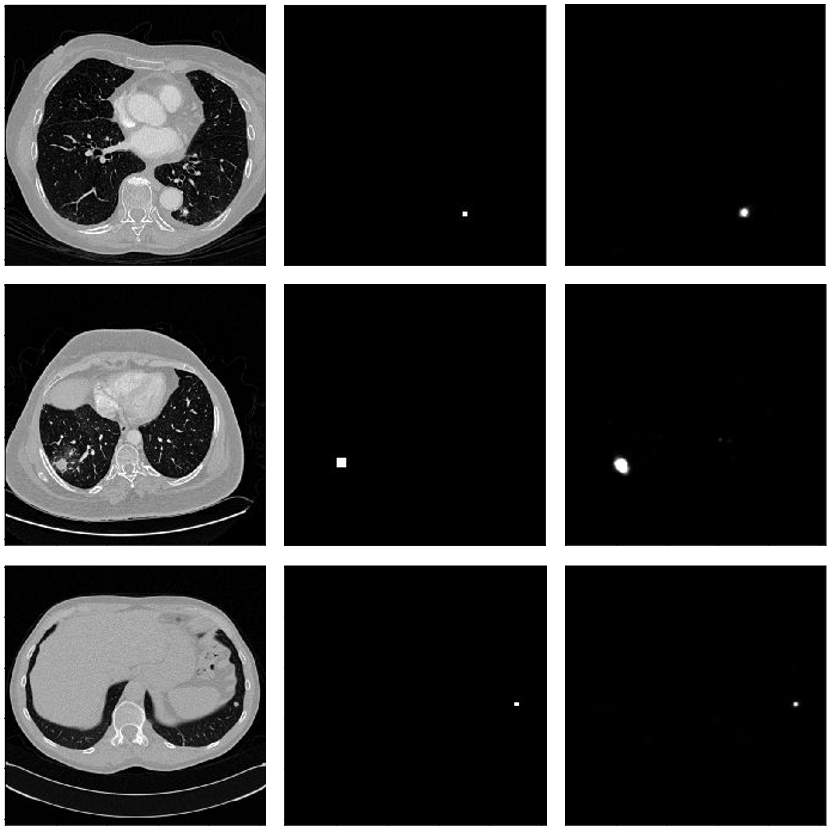

Refer to caption

Figure 8: Segmented results of lung nodules. The left image shows the original CT. The middle image is the reference PET image for lung nodule. The right image shows the predicted lung nodule for the original CT image on the left for lung cancer using our segmentation network.

The visualization of few representative examples of segmentation of nodules for lung cancer is presented in Fig 5. In addition, the proposed segmentation network shows highest performance in recognizing the lung nodules is confirmed with the reference PET image which is shown in Fig 8. The comparison of the performance of our proposed encoder with fully connected network outperforms the simple fully connected network and encoder and decoder followed by the fully connected layer.

We carried out additional experiments to show the ability of the proposed segmentation network with positron emission tomography (PET) images. PET images were used as a reference to confirm the reliability of our segmentation network that accurately recognizing the benign and malignant nodules.